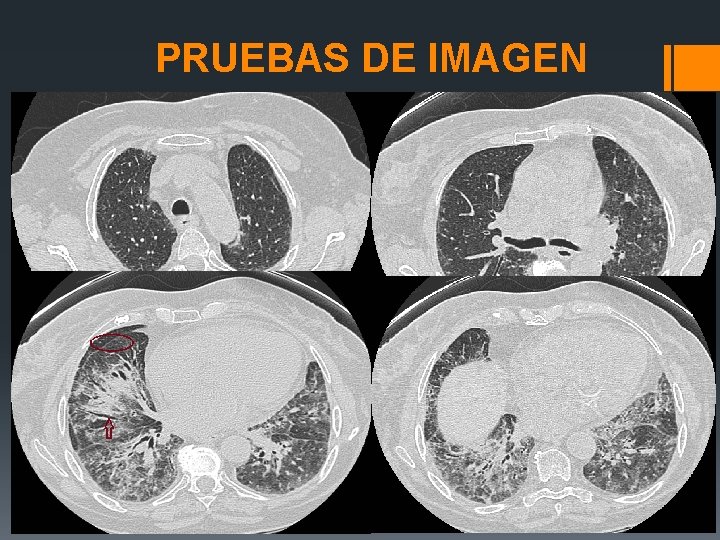

PRUEBAS DE IMAGEN

PREGUNTAS § CUALES SON LOS HALLAZGOS PREDOMINANTES EN EL TACAR DE LA PACIENTE? 1. Engrosamiento septal y peribronquial, bronquiectasias y vidrio deslustrado de predominio basal. 2. Panalización, nódulos, vidrio deslustrado. 3. Consolidación parcheada y opacidades en vidrio deslustrado. 4. Infiltrado intersticial y alveolar nodular.